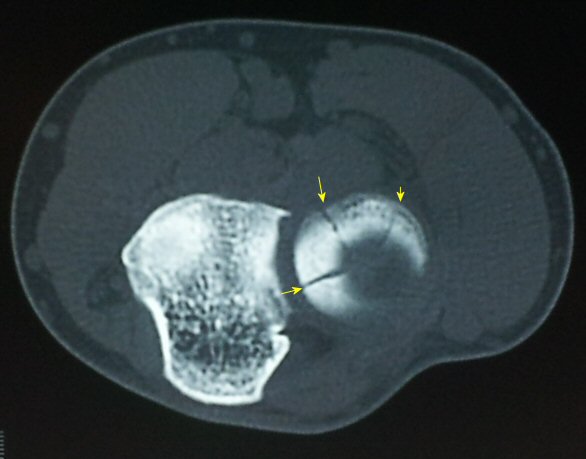

ÀÚ±â°ø¸í°Ë»ç

°ËÇ»ÅÍ ÃÔ¿µ : ¿ä°ñ µÎ ÀåÃà¸é °ñÀý( ±×¸² 6. 7)

¿ä°ñµÎ ¹Ì¼¼°ñÀýÀ» ¾Ï½ÃÇÏ´Â ÃÊÀ½ÆÄ ¼Ò°ß(ÃÖÀçÀÍ ¿øÀåÀÇ ÁÖ°üÀûÀÎ Àǰß)

1) ¿ä°ñµÎ¿Í ¿ä°ñ °æ°èºÎÀÇ ¿¹°¢À¸·Î ÀÌÇà

2) ¿ä°ñµÎ ÇÇÁú°ñÀÇ ºÒ±ÔÄ¥º¯È­

3) ¿ä°ñµÎ¿Í ¿ä°ñ °æ°èºÎ¿¡ ¼ö¾× Àú·ù

4) ¾Æ·§ÆÈÀ» µ¹¸®¸é¼­ ¿ä°ñµÎ Àüü¸¦ È®ÀÎÇÏ¿© ¿ä°ñµÎ ÀåÃà¸é°ñÀý È®ÀÎ